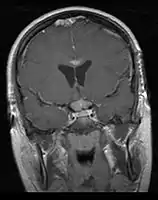

- Mainly located in midline structures, suprasellar region or pineal gland, also basal ganglia and hypothalamus

Location

- Pineal Gland Germinoma

- Suprasellar Germinoma